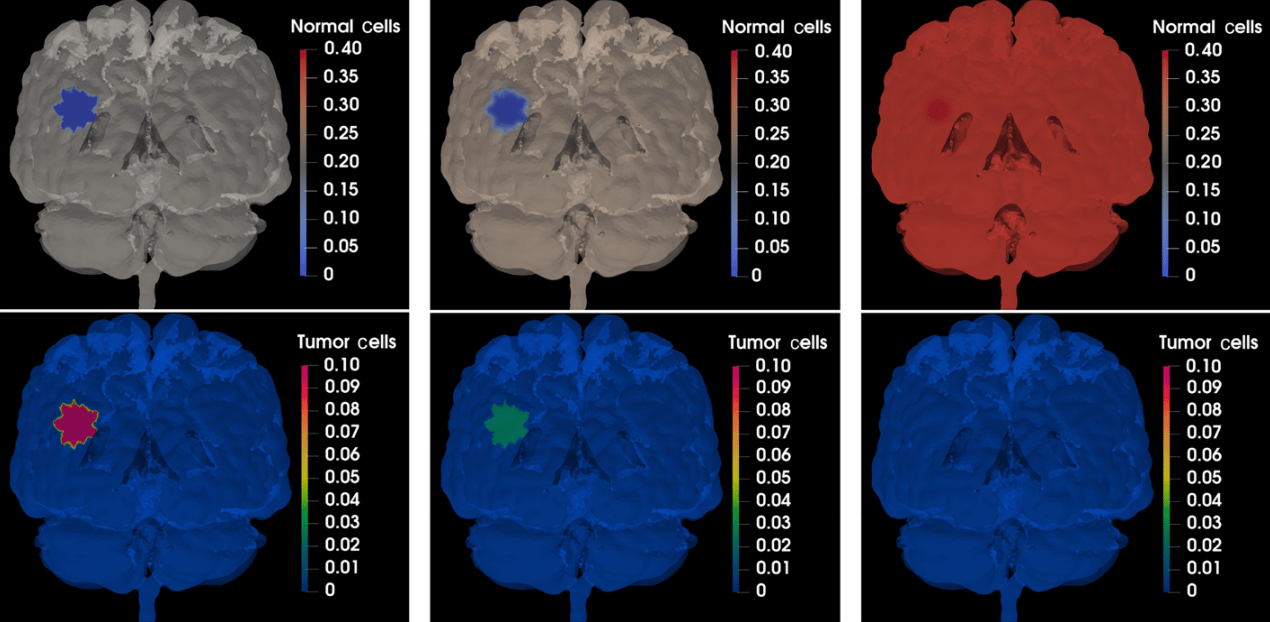

By accurately capturing how the virus spreads and interacts with tumor cells and the immune system, our methods facilitate a deeper understanding of the treatment's effectiveness under various conditions. We observed that the oncolytic virotherapy successfully reduced the size of the tumor until it completely disappeared. These results suggest that the use of oncolytic M1 virotherapy may be an effective treatment for cancer patients, potentially eliminating the need for additional treatments such as chemo-radiation or surgery. The ability to simulate virotherapy dynamics can lead to improved treatment protocols. By predicting how the virus behaves in different tumor microenvironments, clinicians can tailor therapies to maximize efficacy while minimizing side effects.

Response of the tumor to the oncolytic M1 virotherapy at t = 0, t = 32.67, and t = 247.96